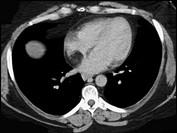

问题 女性,40岁,活动后心慌一年余,彩超发现左心房有异常回声,CT检查如图所示,应考虑为 ( )

选项 A、正常左心房 B、左心房脂肪瘤 C、左心房血栓 D、左心房脂肪浸润 E、左心房黏液瘤

答案 B